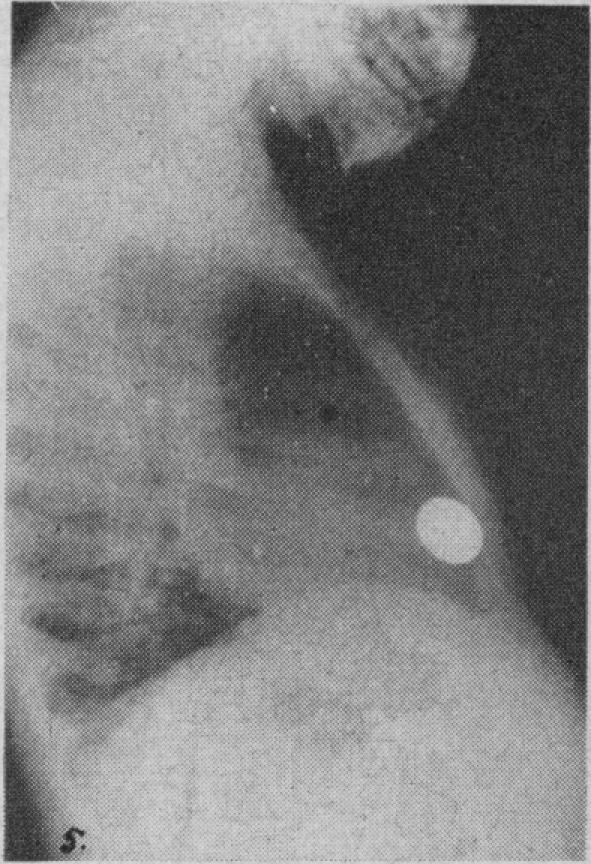

Oesophago-dermato-oesophagoplasty for congenital oesophageal atresia.

Can Med Assoc J. 1951 Feb;64(2):128-31.